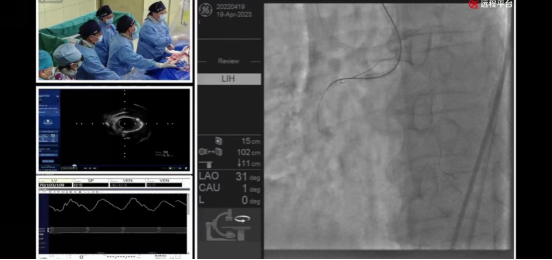

ac米兰官网中文网站附属第一医院心血管内科介入团队—井玲教授、涂应锋教授、盛力教授、董国教授、曹阳副教授、石治宇副教授、王定宇主治医生,首先展示了在冠状动脉CTA三维重建技术(原创性技术)指导下,应用逆向技术成功开通右冠状动脉慢性完全闭塞病变,并通过双球囊-导丝交错切割技术(原创性技术)有效处理球囊不能通过的病变,顺利置入2枚支架。

ac米兰官网中文网站附属第一医院心血管内科介入团队—公永太教授、赵继义教授、李俭强副教授、孙党辉副教授、张松副教授、王定宇主治医生,展示了基于冠状动脉CTA三维重建技术(原创性技术)制定的术前手术策略。术中,公永太教授根据术前策略,应用OCT指导冲击波球囊处理前降支重度钙化病变并成功保护闭塞高危对角支,顺利置入2枚支架。